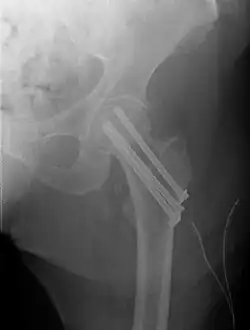

Closed reduction may not be satisfactory and open reduction then becomes necessary.[43] The use of open reduction has been reported as 8-13% among pertrochanteric fractures, and 52% among intertrochanteric fractures.[44] Both intertrochanteric and pertrochanteric fractures may be treated by a dynamic hip screw and plate, or an intramedullary rod.[43]

The fracture typically takes 3–6 months to heal. As it is only common in elderly, removal of the dynamic hip screw is usually not recommended to avoid unnecessary risk of second operation and the increased risk of re-fracture after implant removal. The most common cause for hip fractures in the elderly is osteoporosis; if this is the case, treatment of the osteoporosis can well reduce the risk of further fracture. Only young patients tend to consider having it removed; the implant may function as a stress riser, increasing the risk of a break if another accident occurs.